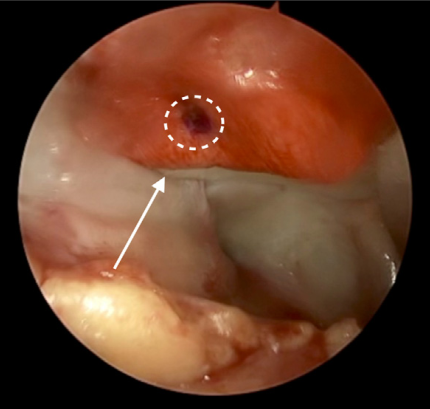

Chúng tôi sử dụng bộ dụng cụ Chondrectom Extended dành cho khớp lớn (Biovico, Gdynia, Ba Lan) để làm sạch vùng tổn thương sụn. Việc nạo sụn được thực hiện bằng các dụng cụ chondrectome mặt trước và bên, cho phép tạo và làm rõ viền sụn ổn định — đây là bước quan trọng để phục hồi sụn thành công. Chondrectome song song được sử dụng để loại bỏ các gai xương trong tổn thương hoặc vùng sụn đã canxi hóa. Sau đó, dùng thìa nạo để làm sạch đáy vùng tổn thương đến vạch phân giới giữa sụn và xương (tidemark), dựa trên cảm giác âm thanh và xúc giác để xác định khi nào đã nạo đến xương lành⁵. Dấu hiệu chảy máu dạng chấm nhỏ là chỉ điểm cho thấy độ sâu nạo phù hợp (Hình 3).